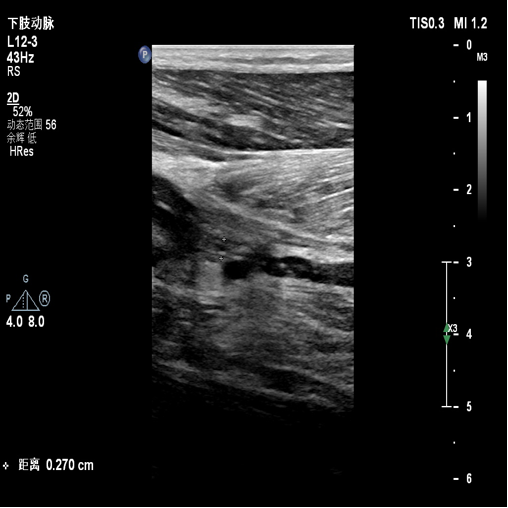

图:胫腓干血栓及直径

胫后及腓动脉起始处彩色血流图